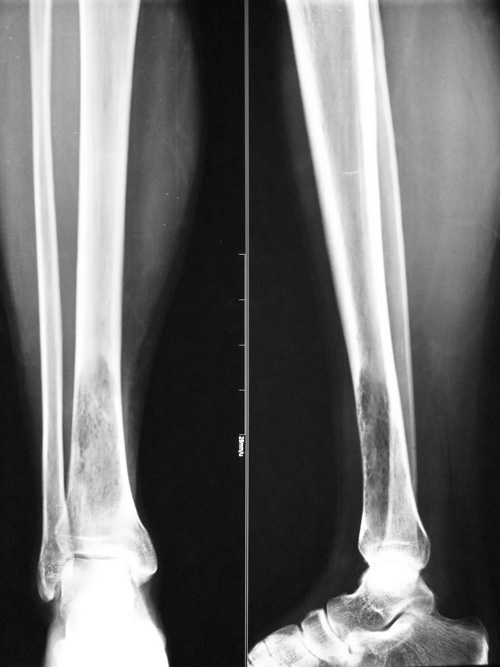

男 26岁

右小腿肿物数年,近期疼痛加重。

胫骨下端骨髓腔内局限性骨密度减低改变,边界模糊,骨皮质未见明显中断,结合病人多年的病史,考虑软组织良性肿瘤压迫吸收临近骨组织。建议mr或ct检查。

胫骨下段密度减低,呈丝瓜瓤样改变,髓腔稍扩大,皮质略变薄,骨膨胀不明显,无骨变形,考虑骨纤可能

病变边缘清晰,似有硬化环。邻近骨皮质连续,未见中断。周围未见软组织肿块。考虑为良性病变。纤维性骨皮质缺损或非骨化性纤维瘤。

病理结果,腺泡样软组织肉瘤!

腺泡样软组织肉瘤